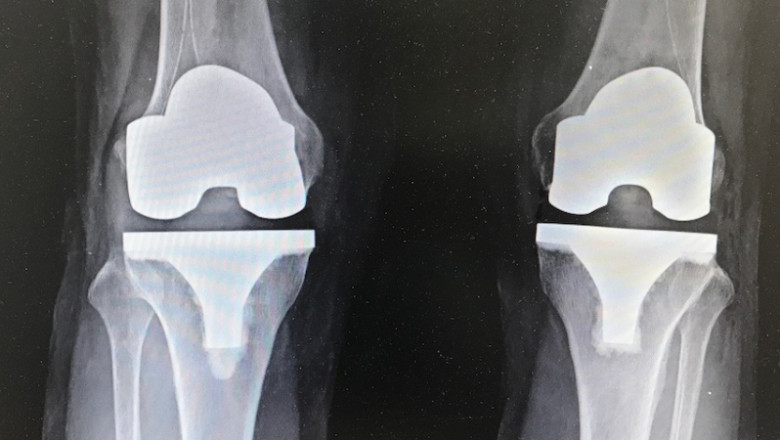

3. Bilateral knee replacement: both knees replaced

After that we will conduct our surgery procedure as per the requirements. We will remove the damaged surfaces of the knee joint and replace with the prosthesis. The knee prosthesis made up of metal and plastic. The most common type of artificial knee prosthesis is a cemented prosthesis. Once the surgery done, patient can walk from the very next day and take a few weeks to get back to normal life.